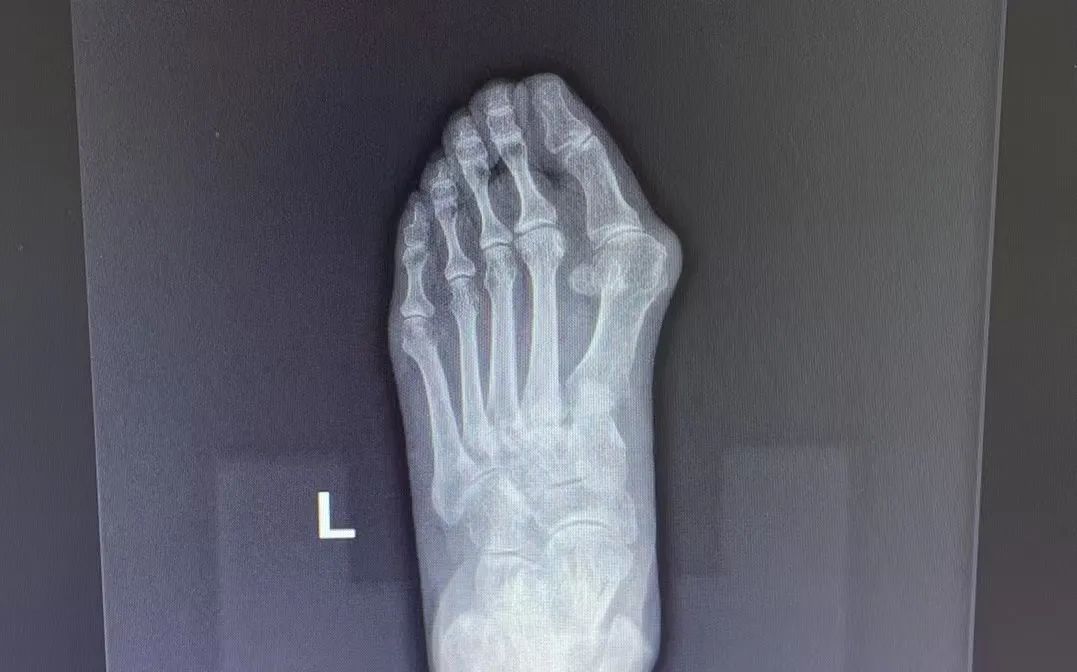

△患者手術(shù)前后比對

對于非手術(shù)干預(yù)無效或嚴(yán)重影響生活質(zhì)量的患者,可考慮手術(shù)干預(yù)。